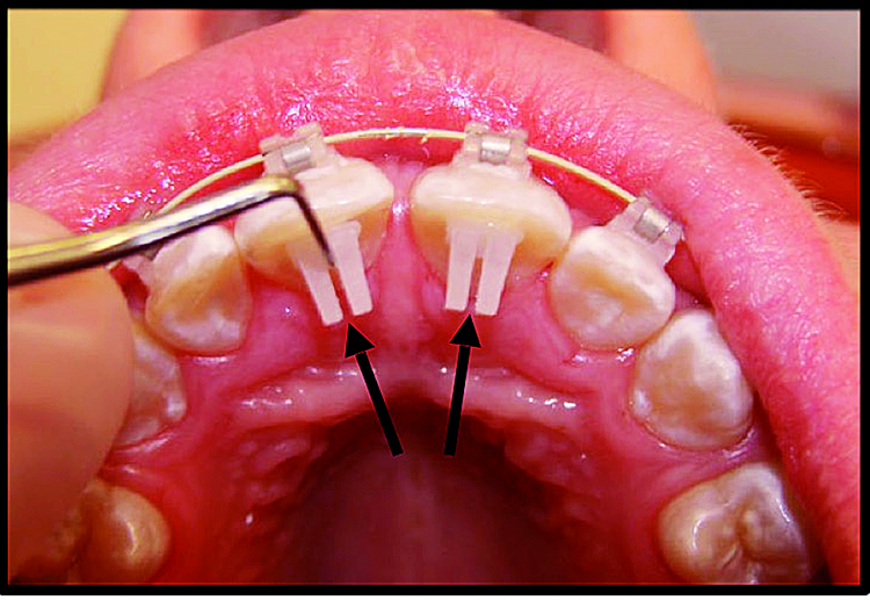

BiTurbo2 system for rapid deep overbite correction